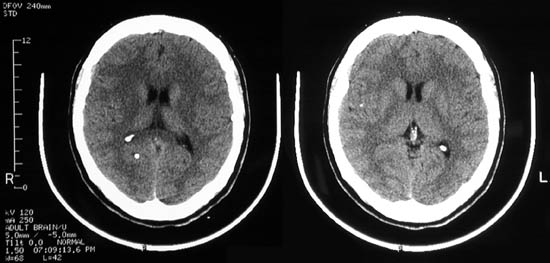

| A bright, rounded lesion is seen in the medial left frontal lobe above. This is a calcifying cysticercus cyst. The organism eventually dies and there can be an inflammatory reaction followed by dystrophic calcification. These lesions may be multiple, as is apparent in the two views below. |